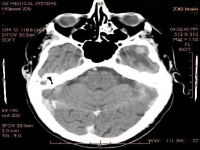

计算机体层摄影(computed tomography,简称CT)是1973年才开始应用临床诊断的X线检查新技术,它具有快速、安全、无痛苦、定位和定性准确的优点,能早期发现较小的病变。由于CT的应用改变了我们对某些病变的认识,如小脑脑干出血脑出血脑梗塞的鉴别诊断等。CT扫描完全或部分取代了既往的创伤性检查,如气脑造影脑室造影脑血管造影,使临床医生能够直观地看到脑室脊髓内病变,大大提高了临床诊断准确率。

CT图像具有比常规 X射线照片高10倍以上的密度分辨率,能够清晰显示病变。CT对颅脑疾病有较高的诊断价值,诸如外伤感染脑血管疾病先天畸形肿瘤等,CT均为首选检查方法。对肝、胰、脾、肾等实质脏器疾病,特别是占位性病变,CT也有较高的诊断价值,若与 B型超声检查配合使用,可达到很高的诊断率。CT对五官盆腔脊柱、四肢、纵隔等部位疾病的诊断也有其独到之处;对肺及消化道疾病的诊断,总的说不如常规 X射线,但有时可起到补充作用。